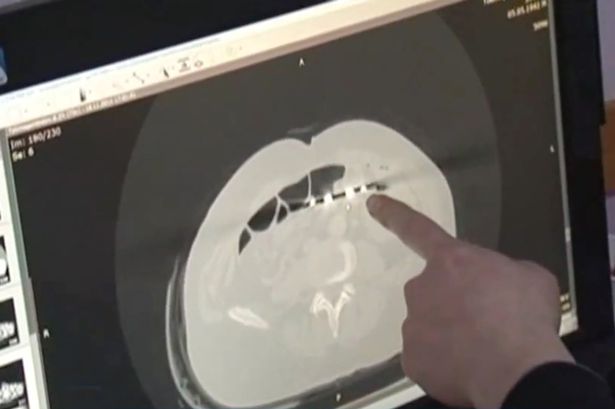

Nesposobni hirurzi ostavili su čovjeka da pati 12 godina od bolova u stomaku nakon što su slučajno ostavili makaze u njemu nakon jedne operacije. Karp Ponomaryov iz Kazahstana prije više od 10 godina podvrgnut je operaciji koja mu je spasila život, ali su mu u trbuhu ostavili makaze duge 20-ak centimetara.

Od tada je ovaj 53-godišnjak trpio strašne bolove nakon obroka, ali se nikad nije žalio na to jer je bio sretan da je ostao živ nakon operacije. Ljekarsku pomoć potražio je ponovo nedavno kada je izgubio apetit i počeo naglo mršati. Doktor Baurzhan Aybaev ostao je šokiran kad je vidio rendgenski snimak.

– Nikad nisam vidio ovakvo nešto. Nekad se desi da ostane neki mali dio hirurške opreme, ali da to budu makaze, to je nevjerovatan propust – rekao je doktor, te dodao: – Hirurgu koji mu je radio operaciju su očito promakle.